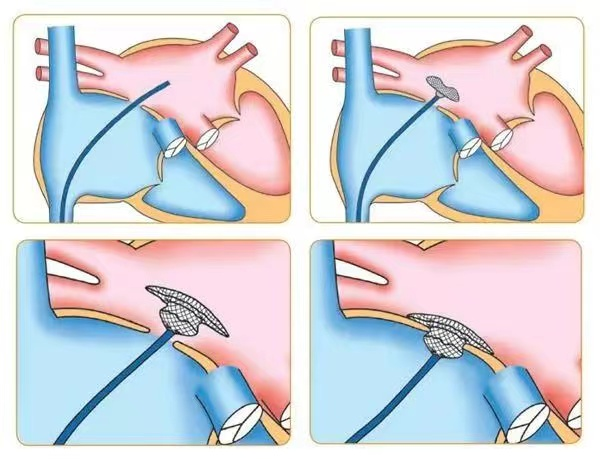

在与患者做好充分的术前准备后,由张曹进主任及李勇主任、黄生华主治医师进行介入手术,心血管内科团队互相配合,术中局部麻醉,从大腿根部的股静脉做一个穿刺,仅在患者身上切开一小道的伤口,由此引入封堵器装置,在透视下及超声检查下证实房间隔缺损封堵器位置良好,房缺完全封堵,无残余分流。手术仅半小时,就顺利完成手术,术后患者转入CCU监护治疗。

李勇主任表示,房间隔封堵术采用经股静脉穿刺的办法,将封堵伞片送至心房,修补位于左右心房间的缺损处,阻断心房水平的左向右分流,恢复正常的血液循环。相较于房间隔修补术,房间隔封堵术其优点是创口小,痛苦小,恢复快,避开了开胸、体外循环、心脏停跳等环节,手术全程由超声引导,实时了解心脏情况,判断手术效果,手术成功率高,现已广泛成熟应用于临床,房间隔缺损、室间隔缺损、动脉导管未闭等先天心脏疾病,均可以采取介入封堵方式治疗。

房间隔缺损封堵术示意图